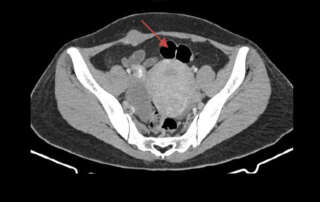

A parasitic fibroid and adhesions due to abdominal hernia surgery with mesh and tacker